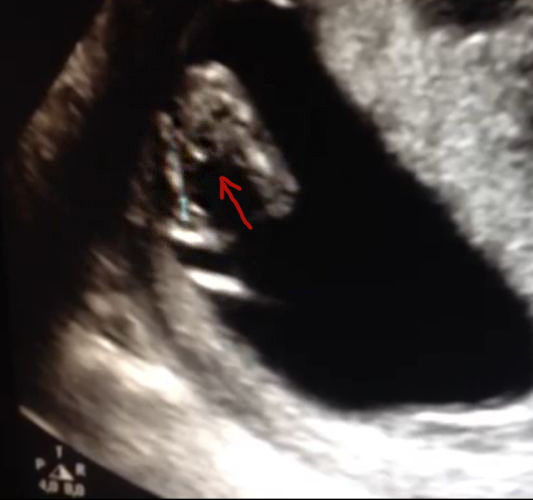

Can someone tell if it a boy or a girl? or is this picture not yet good enough? Thanks already! -XAttachment 13649

Was she given a nub shot? I'm not seeing anything clear in this pic.

no she dont have a photo with a nub.. :( only this shot between the legs hihi. unfortunately the quality isnt so super from this photo..